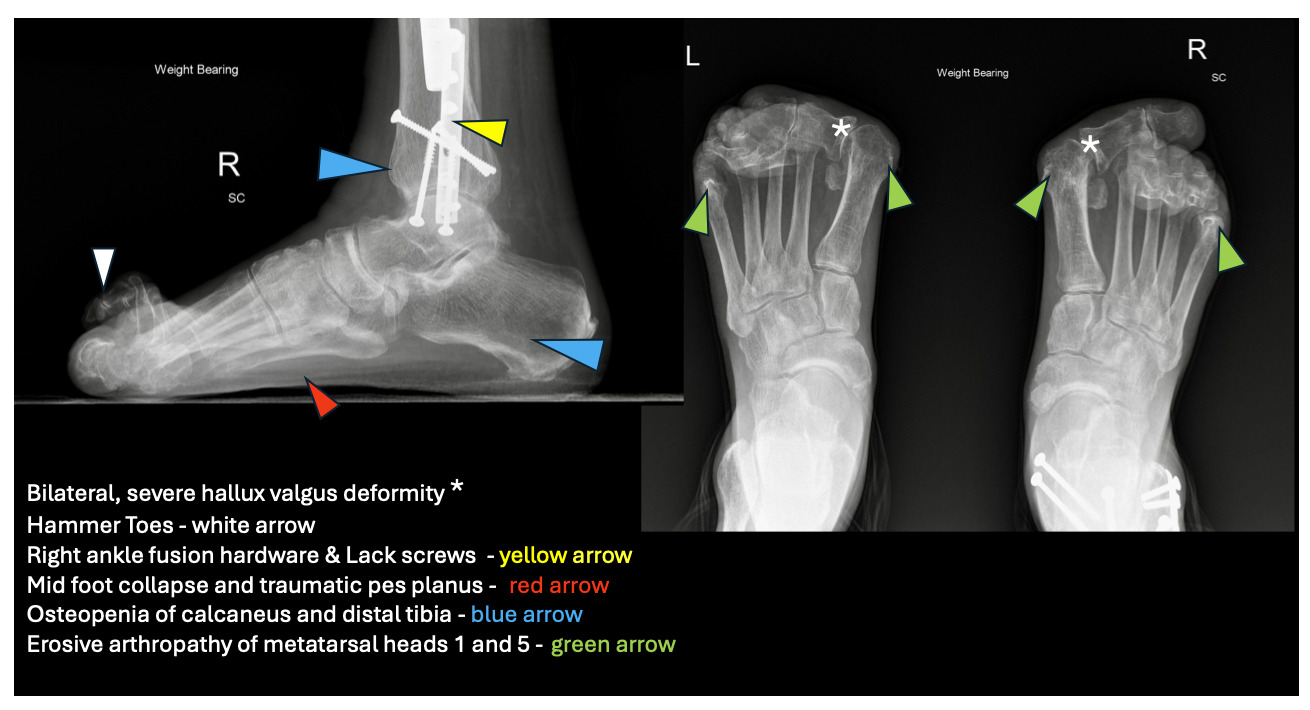

On exam, he had mild dyspnea and cachexia with bitemporal and extremity muscle wasting. His hands showed multiple chronic deformities, including wrist fusion, elbow flexion contractures, Z-shaped thumbs, and swan neck deformities. His feet showed bilateral, severe hallux valgus and multiple hammertoe and claw toe deformities. Weight-bearing radiographs of his feet (Figure 2) and legs confirmed bilateral hallux valgus, moderate bilateral first metatarsophalangeal osteoarthritis, and erosive irregularities of the first and fifth metatarsal heads concerning for erosive rheumatoid arthropathy. Diffuse bony demineralization and bilateral hammertoes were present. A right tibial intramedullary rod and right lateral distal fibular plate with Lack screws in the distal tibia and fibula, consistent with right ankle fusion, was noted.

Genetic predisposition and toxins, such as cigarette smoke, activate an autoimmune response that results in anti-citrullinated protein antibodies and other pro-inflammatory cytokines, leading to immune activation directed at synovial tissue. Initial manifestations are symmetric, stiff, swollen, and painful joints, worse on awakening. As synovial inflammation worsens, the forefoot is usually the first lower extremity area affected. The progression of lower extremity disease occurred from the forefoot, midfoot, and eventually to the hindfoot. The first MTP joints develop painful, progressive bunions, called hallux valgus deformity. Progressive inflammation and ligament destruction of the metatarsophalangeal (MTP) joints result in characteristic subluxation. Toes dislocate upwards at the ball of the foot, pushing the metatarsal heads downward and creating painful calluses (Figure 1). The upward curling of the phalanges creates claw and hammer toes. Ligament weakening eventually causes midfoot collapse and pes planus. Hindfoot deformities manifest as ankle instability and pain. Surgical arthrodesis (Figure 2) is often associated with pain relief and improved mobility.4